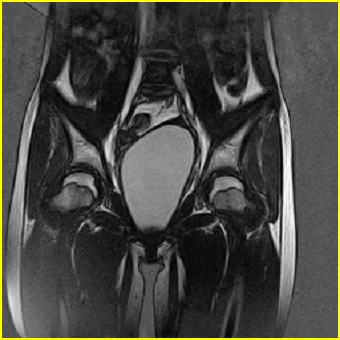

女、15岁、下腹疼痛2天,排尿困难1天。查体:处女膜闭锁,距处女膜约4至5cm处扪及一约5cm直径的圆形包块,张力较高,触痛明显、欠活动。b超提示子宫增大伴宫内增强回声团。

影像意见:子宫直肠陷凹积血。

更正影像意见:阴道积血。

处女膜闭锁,阴道积血

处女膜闭锁,阴道积血,子宫积血.

阴道积血,子宫积血.

子宫及阴道积血。

处女膜闭锁,伴子宫及阴道积血.